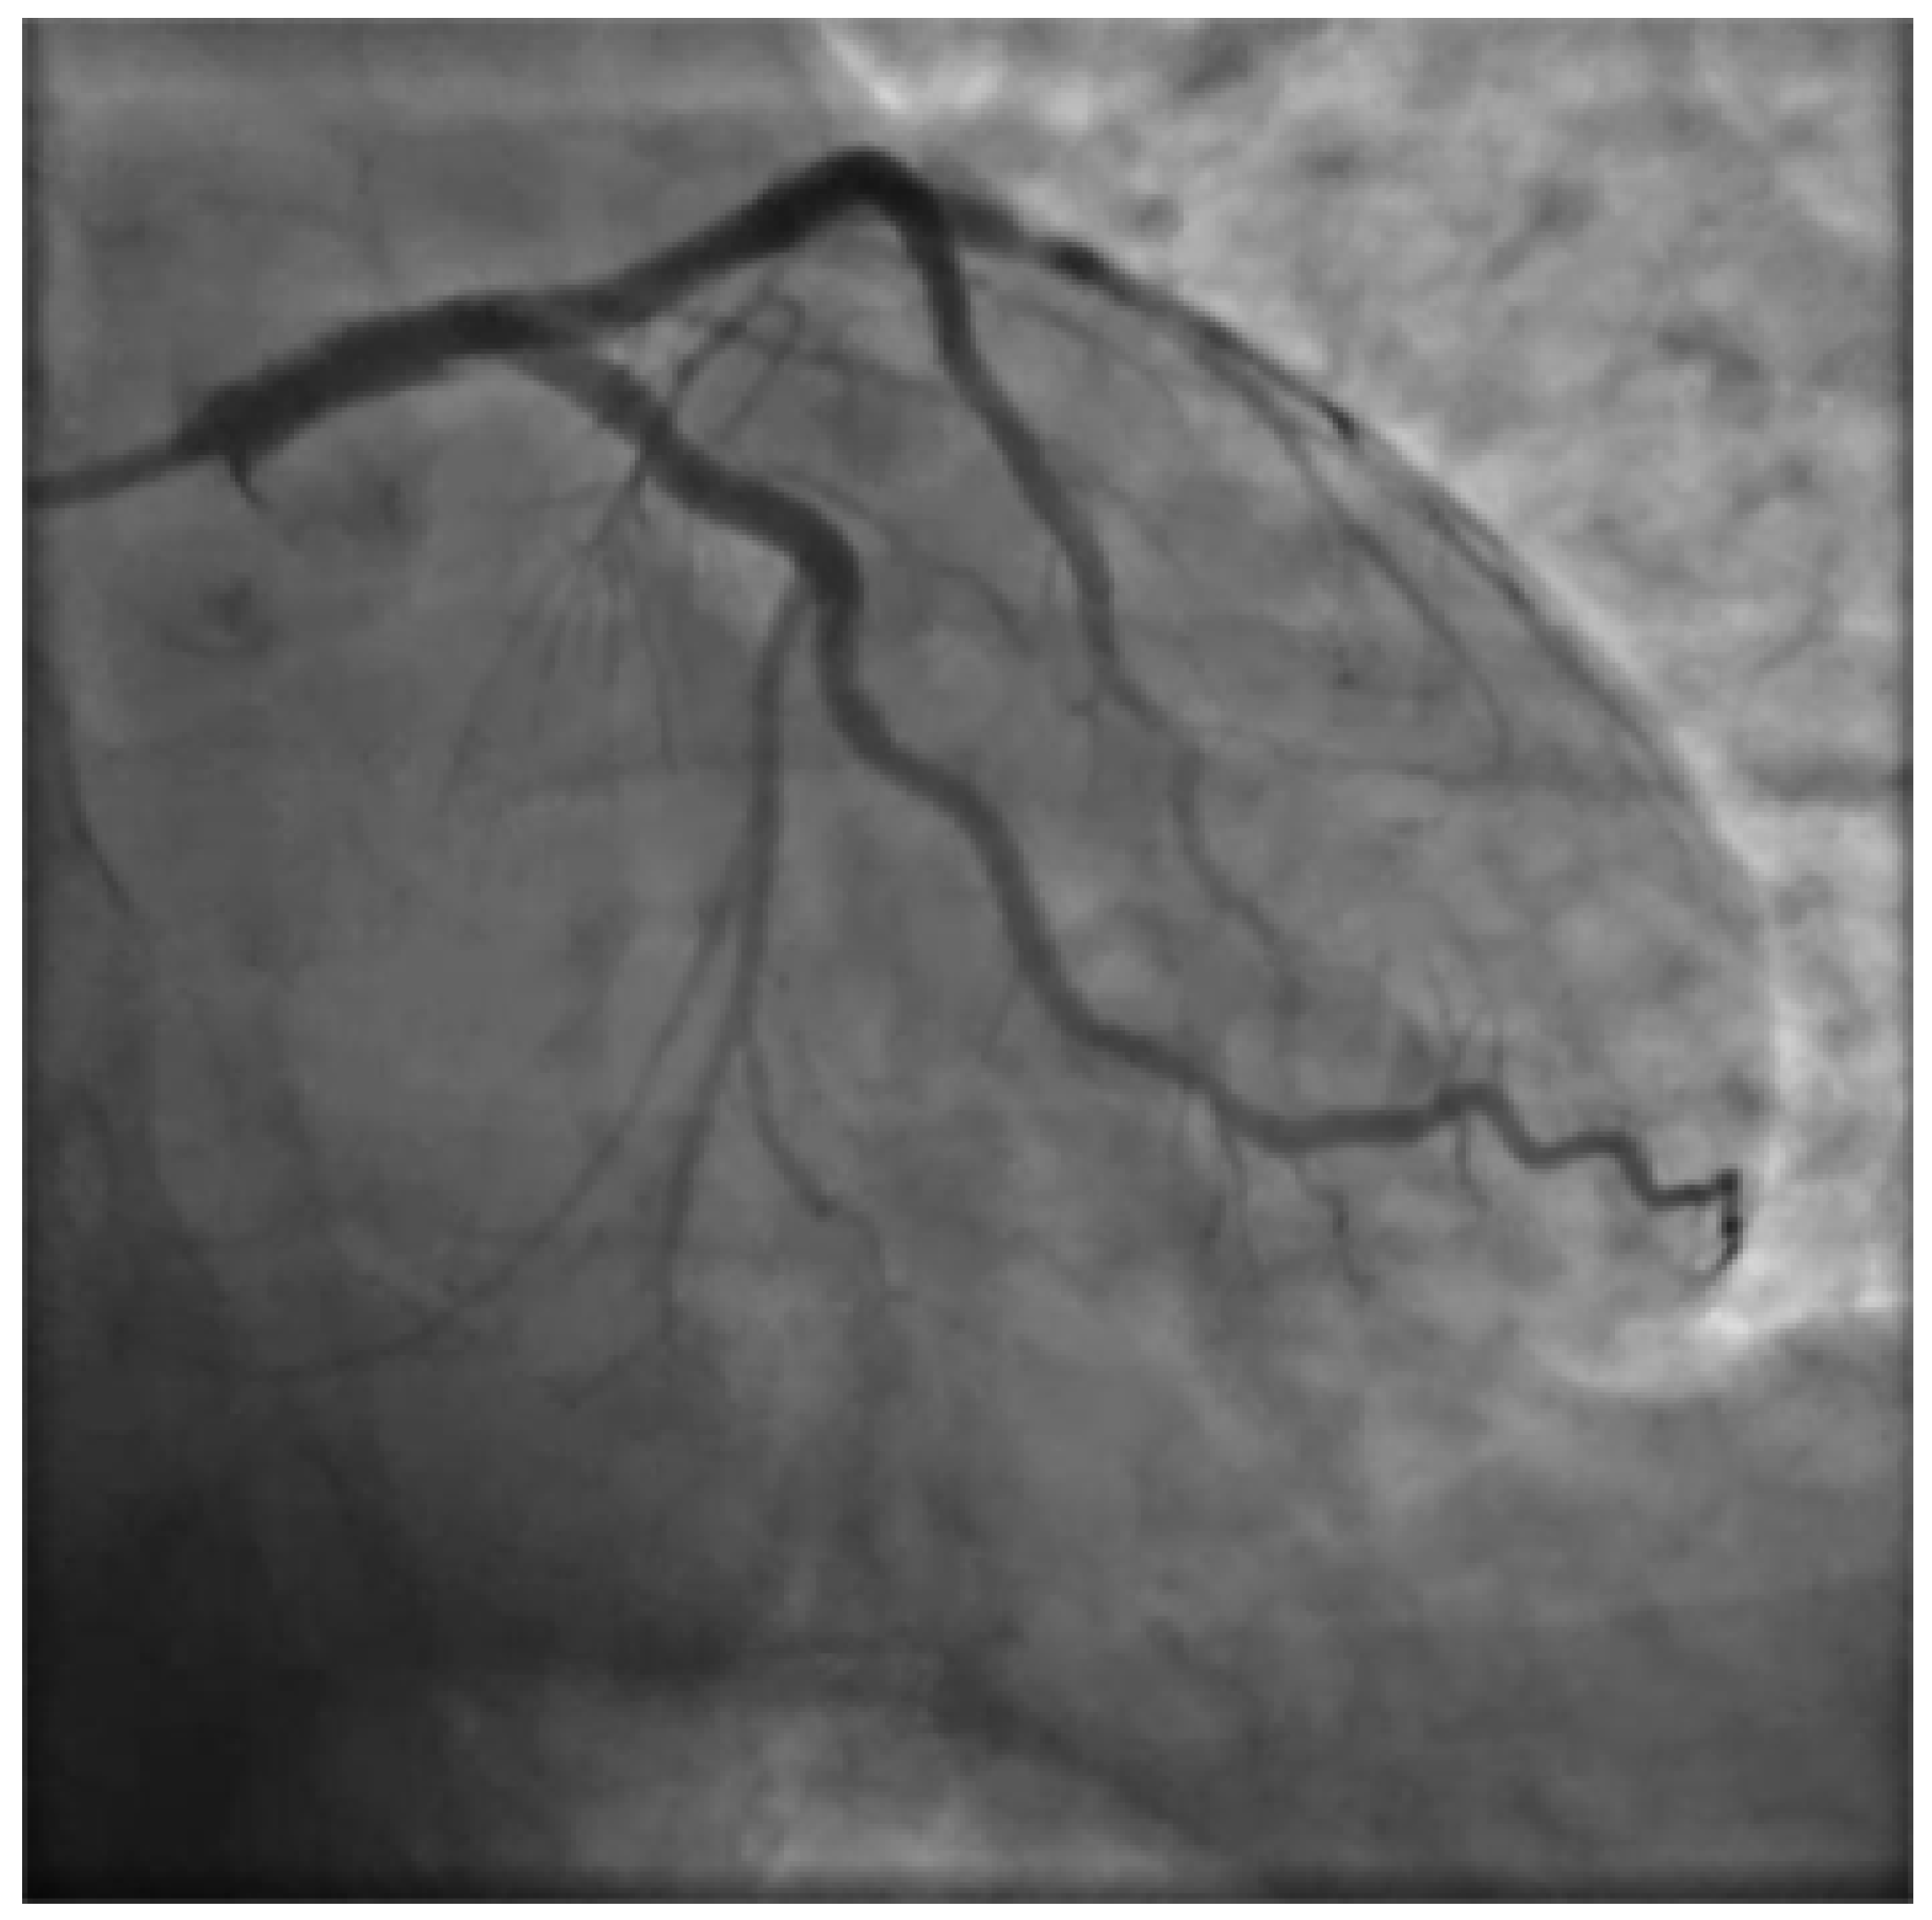

Figure 6. Final result after I procedure PA caudal.

Figure 7. Final result after I procedure PA cranial.

A decision to accept wire position was made and stenting was initiated starting with distal stent placement followed by LM-LAD stenting in order to trap hematoma. Finally stenting of LAD-DG bifurcation (involved in the dissection) with mini-crush technique was done. A decision was made to stent the LCx ostium too, as hematoma migration led to severe ostial stenosis compromising definitive stabilization. Such stenting was achieved with the T and small protrusion technique. All stenting was achieved with II generation drug eluting stents namely Medtronic Resolute Onyx. The final angiographic result was excellent, the ECG showed ST resolution and the patient's hemodynamics rapid improvement (Figure 6 and Figure 7). Loading dose ticagrelor was administered orally at the end of the procedure.